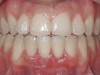

CASE 1 Fig 2. Pre-treatment clinical view of a 28-year-old patient with Miller Class I recession of the lower left central incisor treated with conservative SPT.

Figure 2

When the tooth is properly aligned within the arch, treatment is managed with reference to Miller’s classification.7 Because most post-orthodontic GR cases are classified as Miller Class I and II defects, the authors focus on the management of these two classes only, and within the scope of this article, Miller Class III and IV defects are not addressed. Surgical root coverage of both Miller Class I and II defects is one treatment choice. However, in Miller Class I cases, a conservative approach can be considered, as well. Such an approach consists of supportive periodontal treatment (SPT)—professional periodic deposit removal every 2 to 3 months during a 1- to 2-year period. The authors’ clinical experience shows that spontaneous root coverage may occur following this conservative approach, particularly in young patients (Figure 2 and Figure 3). Similar results have been reported in a 3-year prospective study in which recession defects healed spontaneously following improvement in oral hygiene standards in children.30 In cases in which no root coverage is observed at the end of the follow-up period, surgical root coverage can be considered.